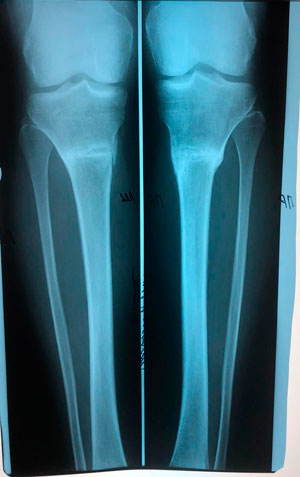

Пациентка - 37 лет.

Дата операции - 24.10.2019г.

Диагноз: варусная деформация голеней. Ротация с обеих сторон.

IMG_6691-25-10-19-11-13.JPG

IMG_6693-25-10-19-11-13.JPG